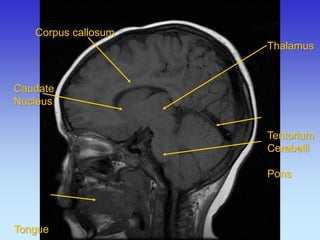

Caudate

Nucleus

Tongue

Corpus callosum

Thalamus

Tentorium

Cerebelli

Pons